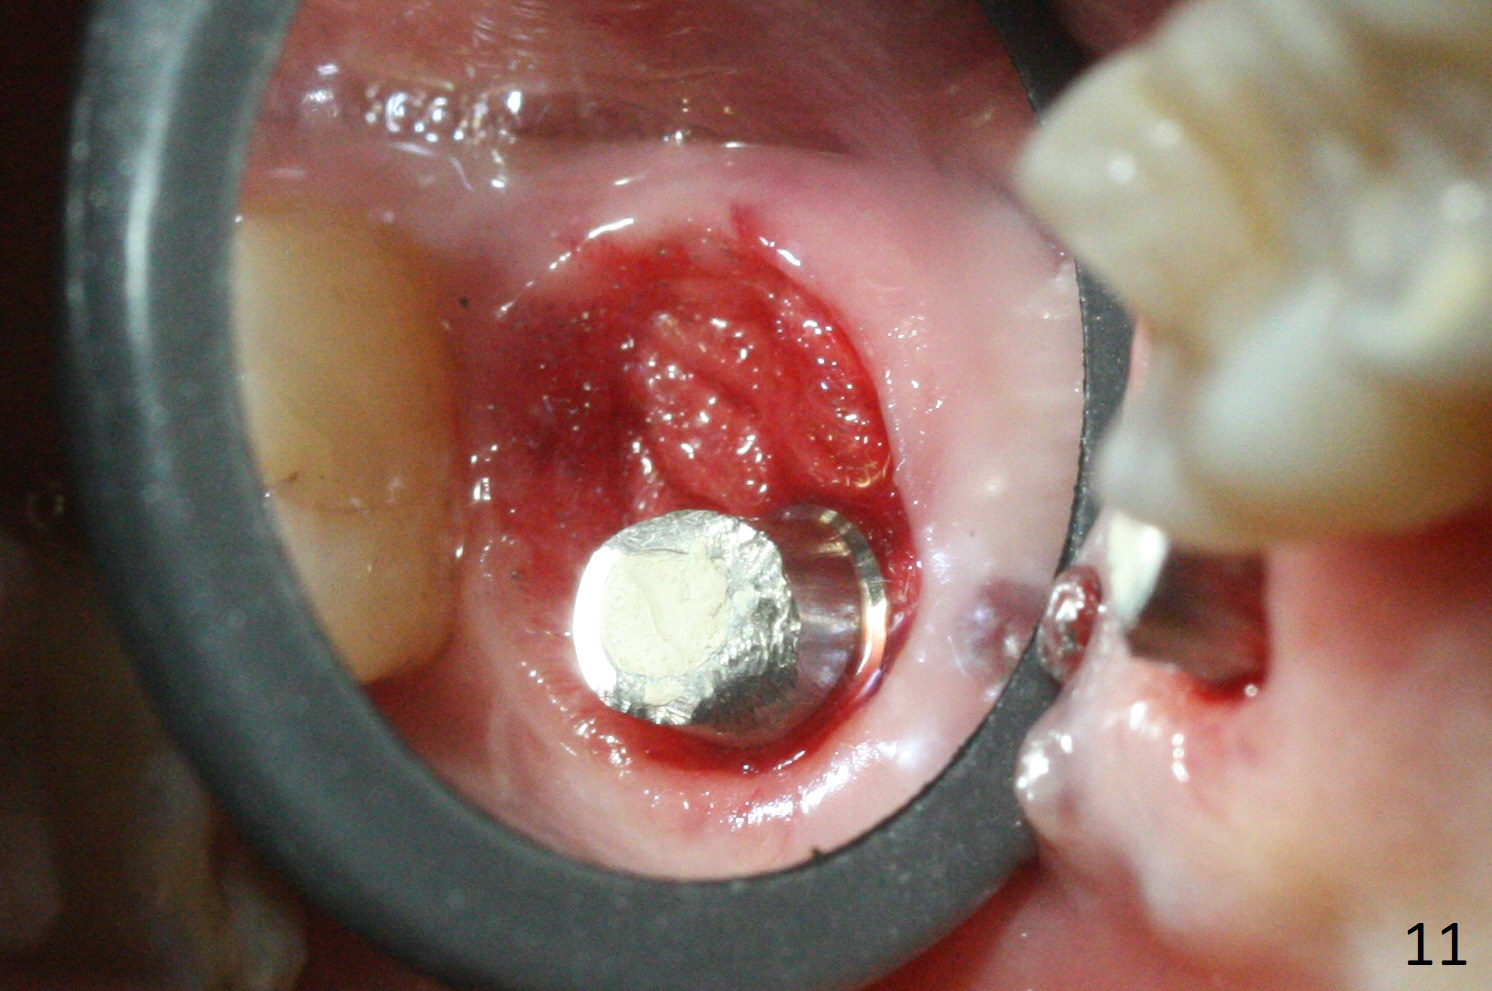

There is a fistula distal to the tooth #2 with deep pocket distopalatally (Fig.1 *), corresponding to palatal root fracture (Fig.2). There is a septum (Fig.3 S) between the buccal (B) and palatal (P) sockets. Osteotomy is initiated in the center of the septum (Fig.4 black circle). In fact the center of the socket is buccal (red circle), in which osteotomy should have been established because of the presence of the distopalatal bony defect associated with the root fracture and the distal fistula. The less ideal initial osteotomy leads to palatal placement of the implant and abutment (Fig.11 vs. 12).

Fig.5 shows the mesial slope of the socket (M), which is more or less the center of the socket mesiodistally. If the osteotomy were set up in the red circle (Fig.6) in the mesial slope (Fig.8 green dashed line), the trajectory of 4.5x11 mm dummy implant (Fig.7) would be more ideal (Fig.8 red outline) with more native bone contact. Finally a longer IBS implant is placed (4.5x15 mm, Fig.9,10) to achieve primary stability (50 Ncm). When the provisional is removed for impression 3 months 10 days postop, the implant is found to have been placed distopalatally (Fig.13), which should have been avoided. It appears essential to use guide for a distal implant. It is agonizing to re-encounter the off-axial implant (Fig.14) and the distopalatal access hole (Fig.15) 1 year post cementation. It is also amazing that the abutment screw has not loosened. A fair-sized piece of bone graft has just been removed buccally (Fig.15,16). The patient complains of sensitivity 2 years 3 months post cementation, although there is no abnormality around the implant crown. Guided surgery is essential to avoid restoration complication. There is no thread exposure nearly 3 years post cementation; in fact the apical portion of the abutment is covered by the bone (Fig.17,18).